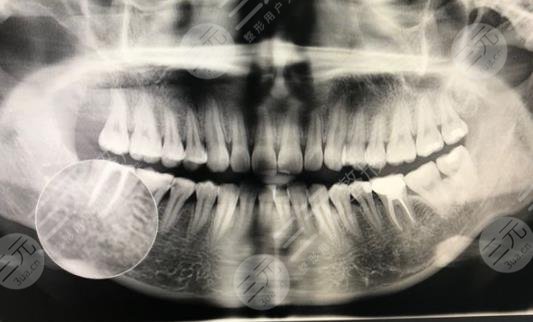

四、南阳口腔医院拔智齿经历分享

相信患有智齿问题的朋友能够明白智齿是怎么样的痛苦吧,那种疼到夜不能寐的感觉,可真不好受,在我支持较严重的时候,我甚至连饭都吃不下去,身体也日渐消沉,家里人就赶快带我来到了南阳口腔医院进行拔智齿,说实话,我的内心是很抗拒的,因为我很不喜欢打针打麻药,这样的东西,但是实在疼的受不了了。

南阳口腔医院拔智齿经历分享

南阳口腔医院的口碑一直很好,所以我的心里还算稍微缓和了一点,到了医院后,医生很快就为我定制了,拔出方案当天就拔出了智牙,拔除之后,总觉得嘴里空空的,但是不疼了,只会有一点点红肿,在麻药劲散过之后会觉得跋涉的地方很痛然后会肿,可能需要一段时间的恢复,大概一星期后就完全恢复了,感觉不到任何的疼痛,现在整个人也开心了很多,吃麻麻香真的很棒,有智齿问题的朋友赶快去解决吧。